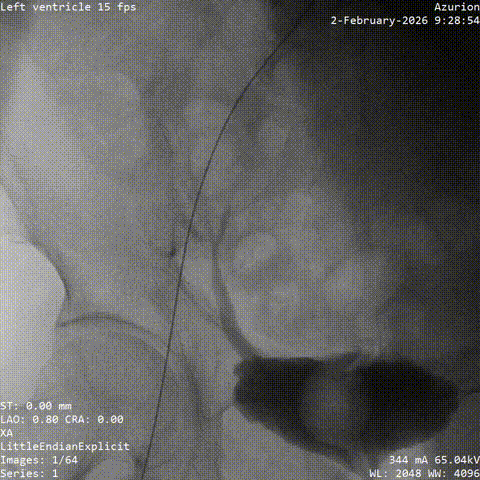

冠脉治疗后一周,张老先生整体状态平稳,进入主动脉瓣置换阶段。团队从股动脉建立通道,将人工瓣膜送至主动脉瓣位置。结合术前评估结果和术中情况,这次手术未进行球囊预扩张,而是直接完成瓣膜释放。

术中,因患者主动脉弓形态较复杂,器械通过一度受阻。团队根据术中情况及时调整策略,最终顺利完成过弓、跨瓣和瓣膜释放。造影及经胸超声显示,瓣膜位置理想、功能良好,左右冠脉血流通畅,未见瓣周漏及血管并发症。

▲根部造影

▲血管扭曲预塑形导丝支撑不足

▲更换导丝后过弓过瓣

▲初始定位

▲左右重合位评估

▲左冠切线位评估

▲最终瓣膜造影

▲入路检查